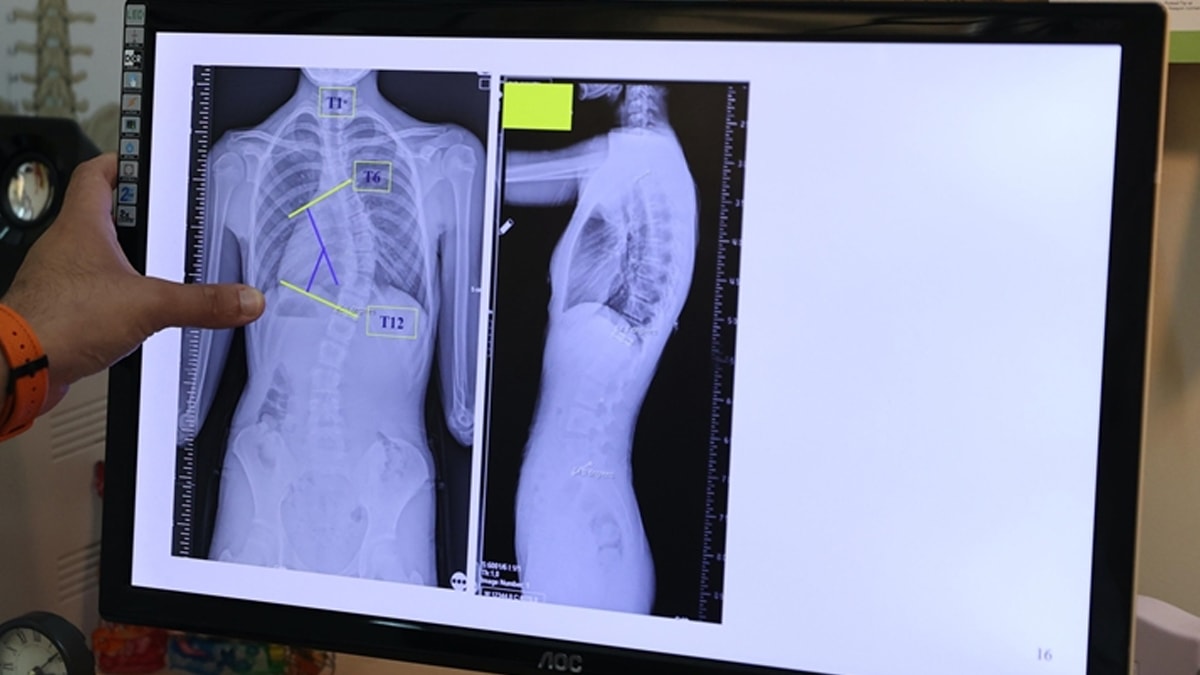

Başaran, yaptığı yazılı açıklamada, skolyozun omurganın üç boyutlu düzlemde sağa ya da sola eğrilmesi anlamına geldiğini, omurgada S veya C şeklindeki bu eğilmelerin yüzde 80'inin nedeninin bilinmediğini aktardı.

"Toplumda 10 dereceye kadar olan omurga eğriliklerine çok sık rastlıyoruz. Bunları normal, postürel eğrilikler olarak tanımlıyoruz. 10 dereceyi geçen eğriliklerde skolyoz hastalığı tanısı koyuyoruz. 20 dereceye kadar olan eğrilikleri 6 aylık aralıklarla büyüme dönemlerine göre takip ediyoruz. 20 dereceyi geçen eğriliklerde ise çocukları egzersiz programına alıyoruz ya da çeşitli korselerle hastalığının ilerlemesini engellemeye çalışıyoruz."

Çocukların hızlı büyüdüğü dönemde önerdikleri korse ve egzersizin, aslında skolyozu iyileştirmeye yönelik tedaviler olmadığını, burada cerrahi sınıra yaklaşmadan hastalığı durdurabilmeyi amaçladıklarını ifade eden Başaran, erişkinlik döneminde 40 dereceyi aşan omurga eğriliğinde cerrahi tedavi önerdiklerini aktardı.